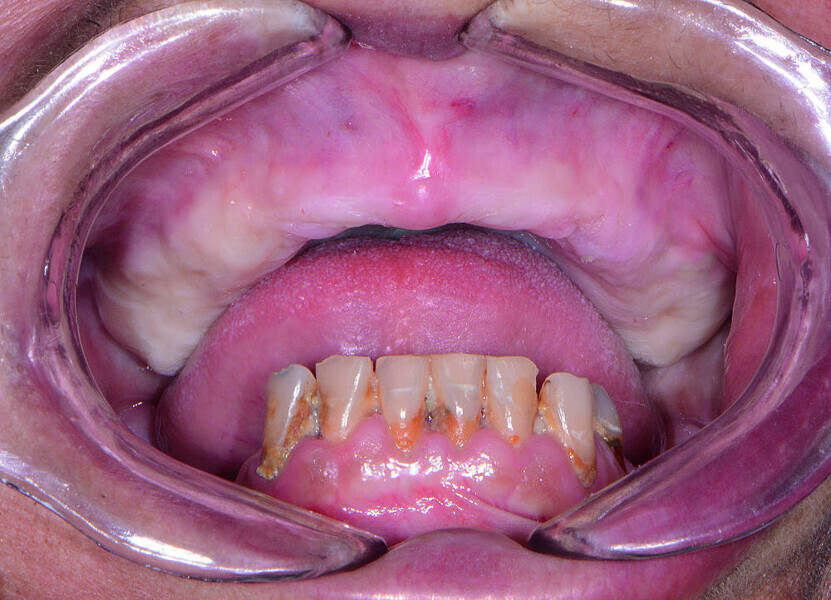

Fig 2 Vue préopératoire avec écarteur de lèvres, sans prothèse